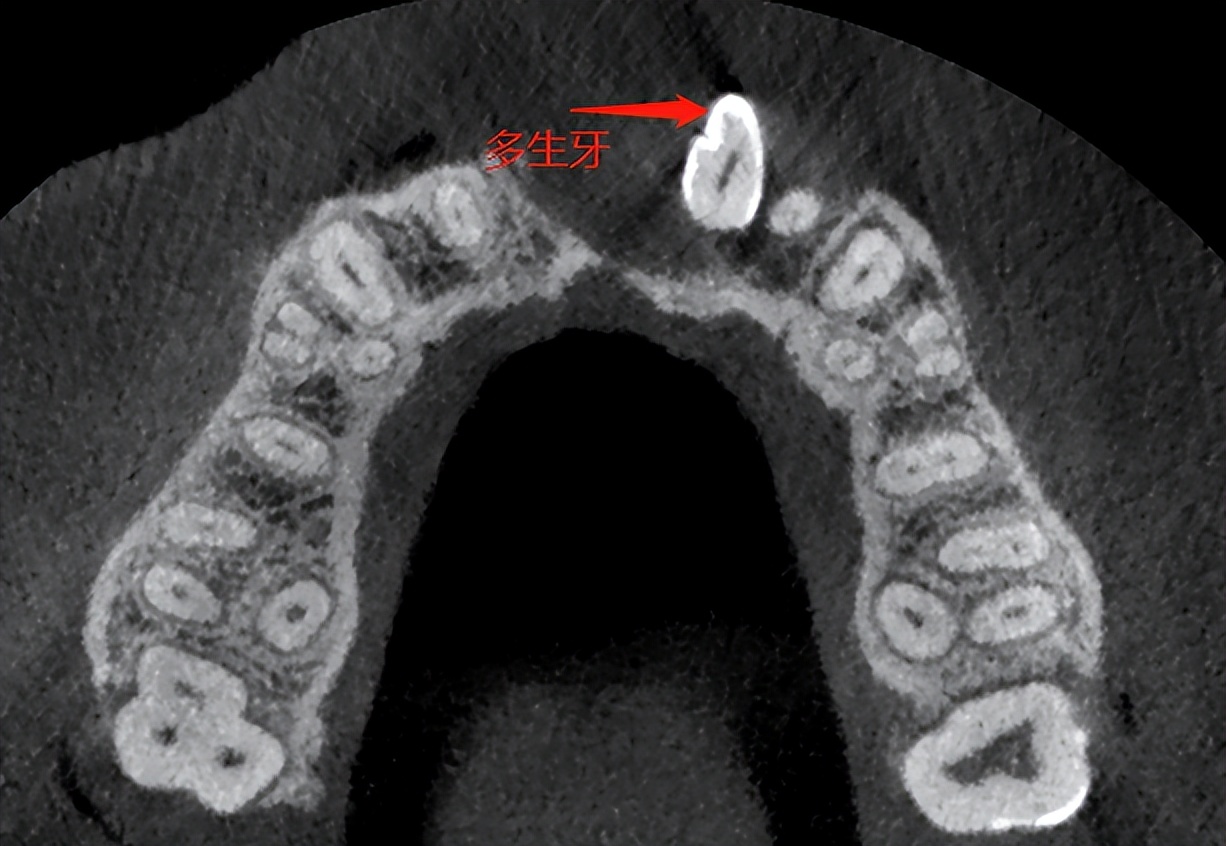

半年前,王女士发现左上颌牙龈凸出,以为是上火引起,口服抗菌药物,未见明显消退。半年期间,凸起越来越明显,连嘴唇也不对称了。期间无任何疼痛不适,也没去医院检查。因非常担心病情的危害,王女士在家人陪同下来苏州高新区人民医院口腔科就诊。医生检查后拍摄口腔CT,发现凸起部位病变范围较大,内含一颗多生牙齿,诊断为上颌骨含牙囊肿,医生建议住院手术治疗。

什么是多生牙呢?就是在正常牙列以外多出来的牙齿,一般好发于恒牙列,乳牙列也可以发生,男性比女性好发,上颌比下颌好发,多生牙的原因现在还不是特别明确。多生牙会导致囊肿?苏州高新区人民医院口腔科主任刘廷忠介绍,含牙囊肿又称滤泡囊肿,发生于牙冠或牙根形成之后,在缩余釉上皮与牙冠之间出现液体渗出而形成含牙囊肿,多来自单个牙胚,临床上见囊肿含一个牙;也可来自多个牙胚,临床上囊肿含多个牙。囊肿生长缓慢,破坏周围骨质,可引起面部畸形。